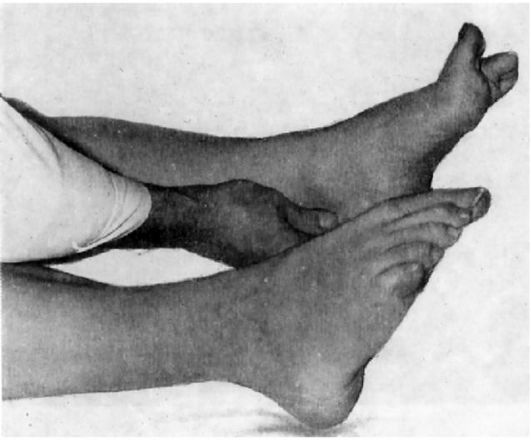

Пирамидная симптоматика в неврологии: ключевые аспекты